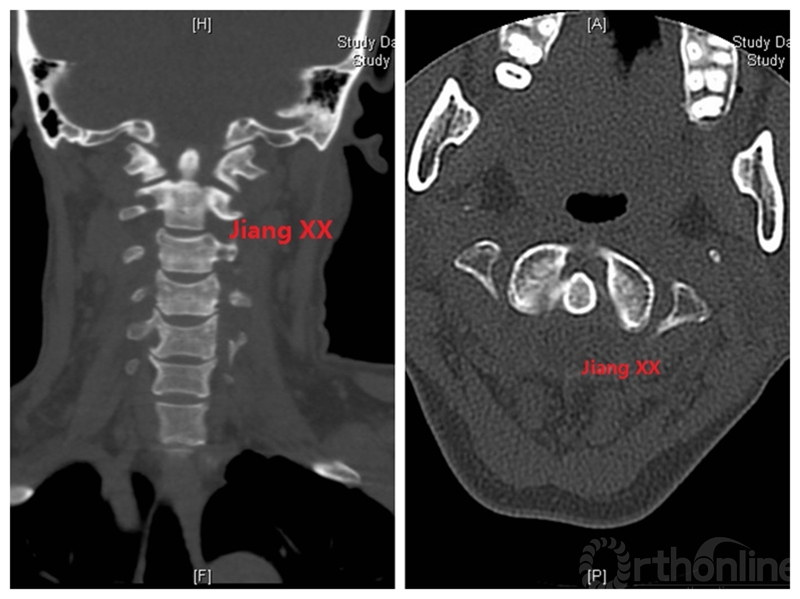

病例二:患者女性,58岁,主因“颈部疼痛伴转头受限半年”入院,诊断为寰枢椎半脱位。

术前CT

术后一年CT